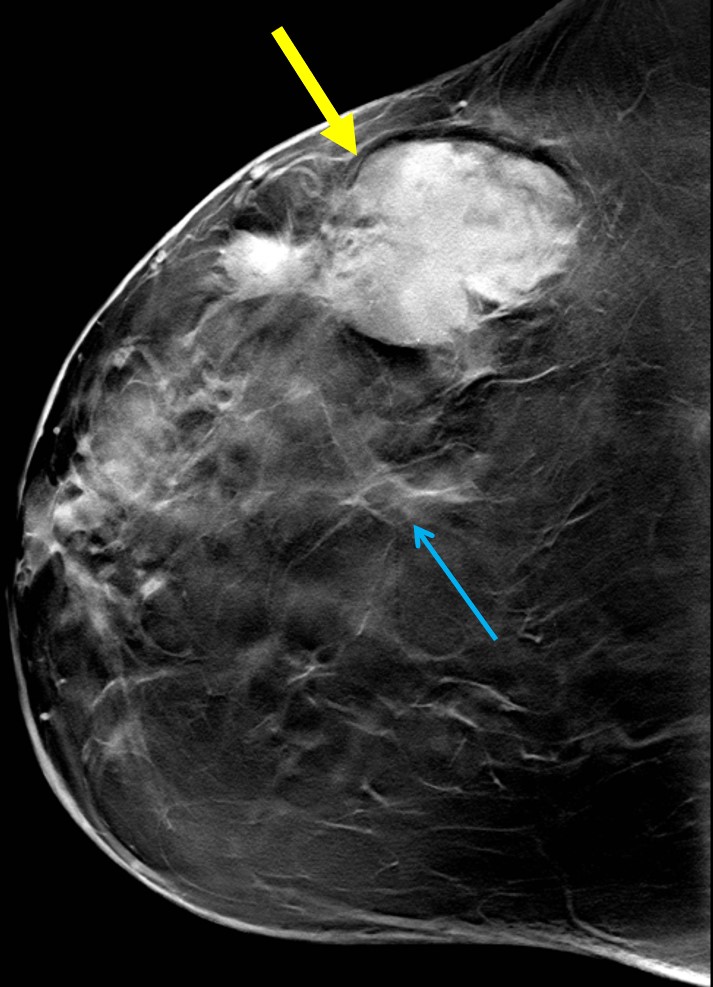

The most common cause of skin metastases in adult women is primary breast carcinoma, which comprises about 70% of cases [1]. Skin metastases have non-specific clinical appearances, making it challenging to differentiate them from other benign conditions [1]. We present a case of a 52-year-old female with type II diabetes and a three-month history of refractory skin lesions who did not respond to anti-inflammatory treatment. The patient subsequently complained of a right breast lump, evaluation of which led to the diagnosis of bilateral synchronous invasive lobular carcinoma.